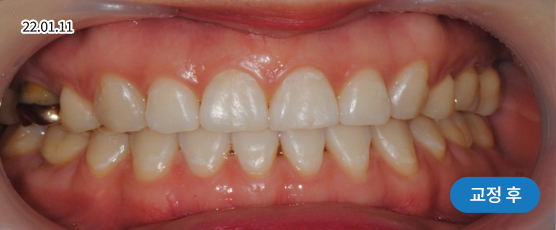

매복치 Solution

매복치는 잇몸 속에서 인접 치아에 손상을 줄 수 있어

치아 견인을 통해 제자리를 찾아주어야 정상적으로 치아가 자리 잡을 수 있습니다.

* 본 사진은 동일 조건에서 촬영되었으며, 환자 본인의 동의를 얻어 게재되었습니다.